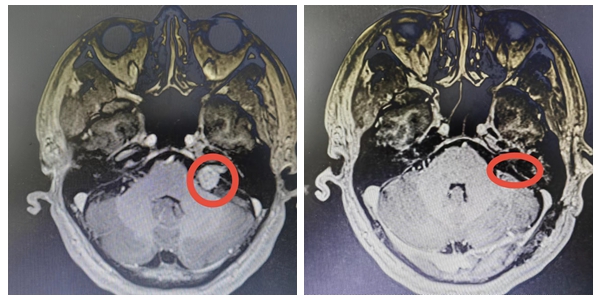

“我在备考神经外科副主任医师时,看见袁贤瑞教授主编的关于听神经瘤的书籍,我就坚定了要找袁教授动手术的决心!”既是神经外科医生又是听神经瘤患者的曹先生说道。 &nb...